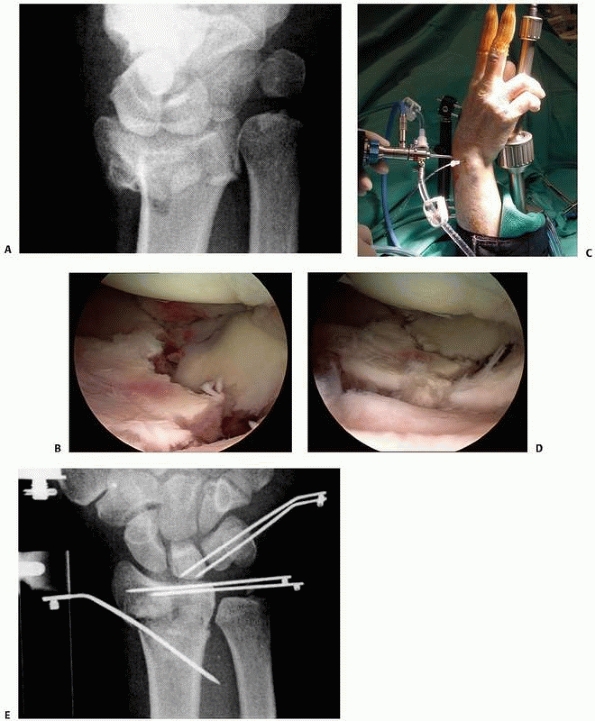

![]() |

FIGURE 30-25 A. Typical three-part intra-articular fracture of the distal radius. B. Depression of the lunate facet palmarly is difficult to reduce by closed methods. C. A plate applied palmarly to the lunate facet reduces and mortars both the DRUJ and the radiocarpal joint.

|